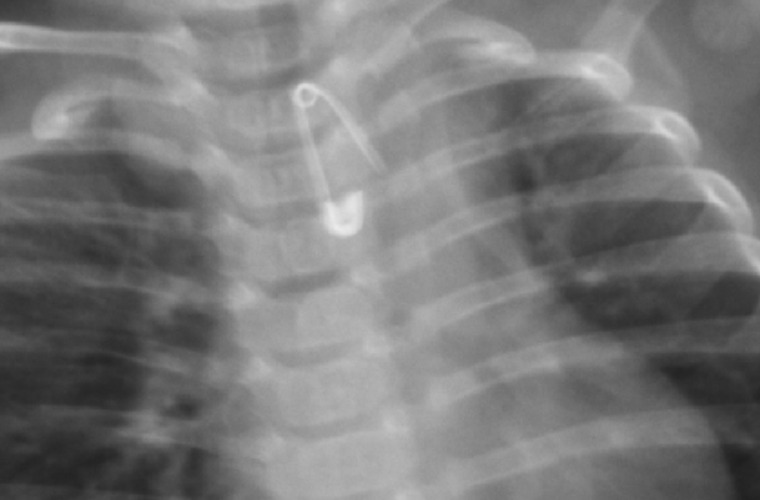

Rodzice z 6-miesięcznym Kubusiem natychmiast wsiedli w samochód i pojechali do szpitala w Krotoszynie. I choć, jak wykazało zdjęcie rentgenowskie - malec połknął 2-centymetrową agrafkę, która, rozwarta, skierowana była ostrzem w dół w przełyku chłopca - lekarka pełniąca dyżur w Szpitalnym Oddziale Ratunkowym w Krotoszynie kazała rodzicom zawieźć chłopca do szpitala w Ostrowie Wlkp. I choć w tym czasie na stanie były dwie karetki kazała im jechać własnym samochodem.